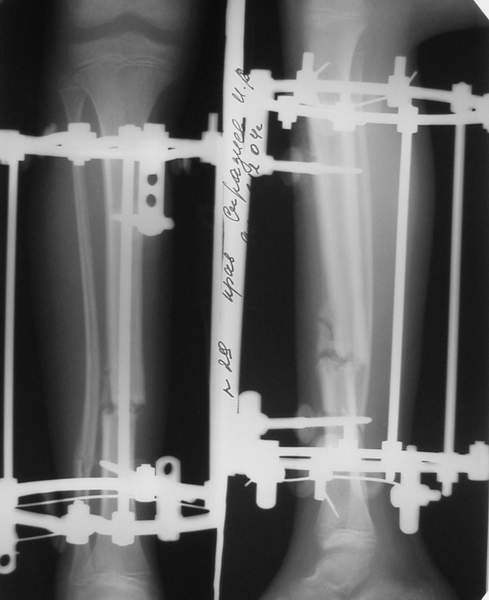

В аттачтах №№ 1 и 2 - примеры, когда 2 кольца не позволили послеоперационно

исправить смещение фрагментов большеберцовой (по ширине и вальгусное).

А казалось бы (#2) - поиграй на штангах и все влетит.

2

3a